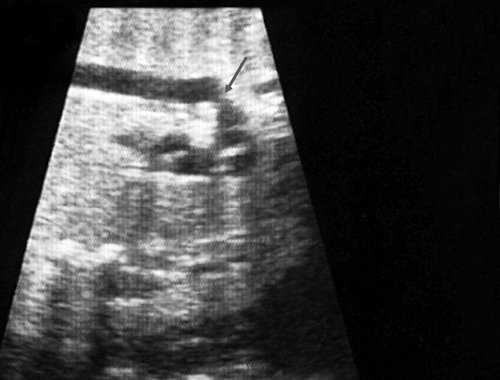

Исходя из особенностей внутрисердечной гемодинамики плода, для диагностики коарктации аорты были предложены косвенные признаки патологии в антенатальном периоде: дилатация правого желудочка и его гипертрофия (см. рис. 3), дилатация легочной артерии [6, 7, 14]. Авторы считают, что это достоверные признаки и встречаются они достаточно часто (в 18 из 24 случаев верифицированных диагнозов коарктации аорты). Поэтому была предложена оценка индексов отношения полости правого желудочка к левому (в норме - 1,1) и легочной артерии к аорте (у здоровых - 1,2). Исходя из увеличения этих параметров, можно предположить наличие затрудненного выброса в аорту или гипоплазию дуги аорты. Тем не менее, по данным предложивших эти косвенные признаки авторов, такие изменения выявляются только в 30% наблюдений (рис. 4).

Рис. 4. Диспропорция размеров желудочков сердца при коарктации аорты. RV - правый желудочек; LV - левый желудочек; AO DESC - поперечное сечение нисходящего отдела аорты.